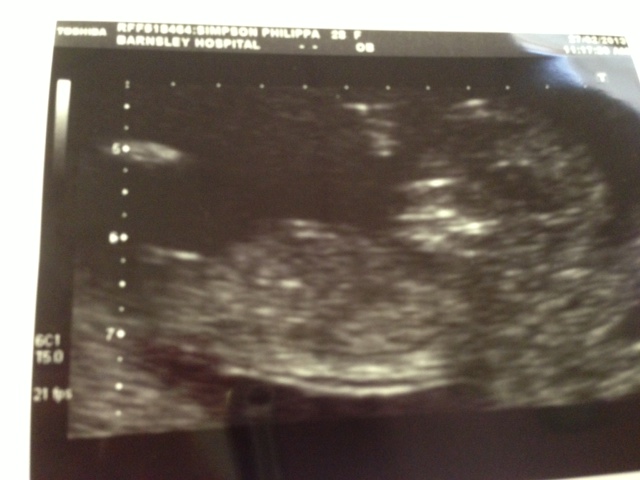

any guesses based on any theory?